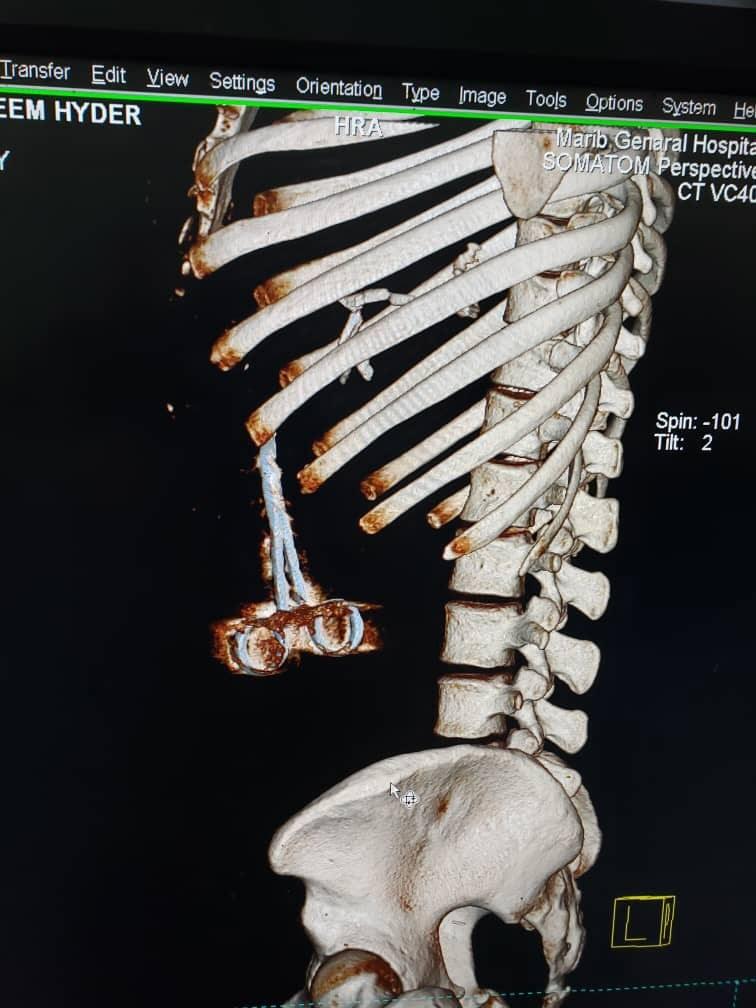

وأثيرت قضية الخطأ الطبي بعد ظهور "مقص" في أشعة مقطعية أجراها الجريح "حيدر"، بعد شعوره المتكرر بألم حاد ومتقطع في منطقة الصدر، ليتفاجأ بالخطأ الكارثي الذي وقع فيه جراحو هيئة مستشفى مأرب، أثناء إجراء عملية جراحية له.

الاشعة المقطعية تظهر المقص داخل جسم الجريح

الأشعة المقطعية تظهر المقص داخل جسم الجريح